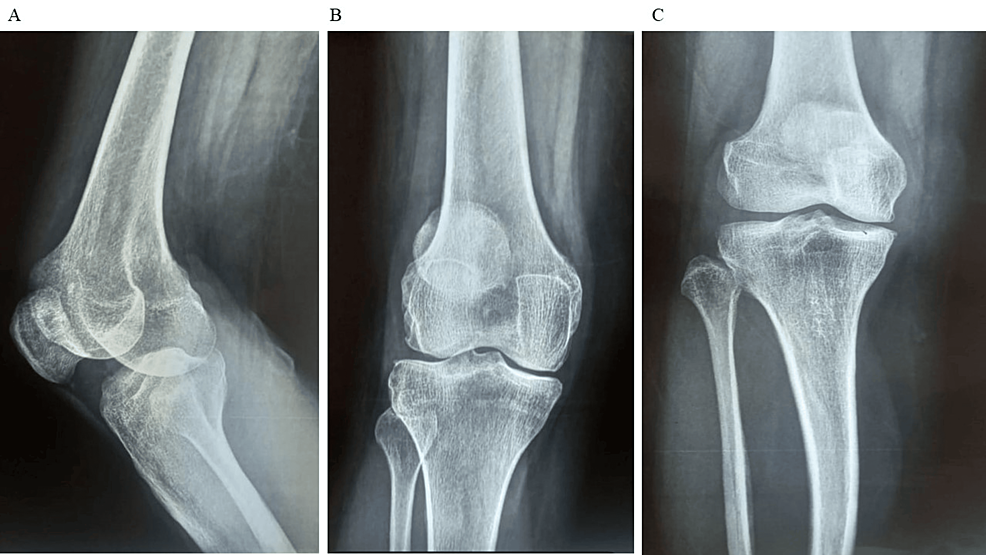

除了骨關(guān)節(jié)炎外,15名參與者還被發(fā)現(xiàn)患有骨缺損,占該隊(duì)列的30%。這些缺損包括各種情況,例如骨折、退行性骨病或先天性畸形,突顯了研究中涉及的骨科問題多種多樣。下圖1顯示了開始干細(xì)胞治療之前的骨骼側(cè)視圖和前后視圖。

診斷的詳細(xì)分布為了解研究參與者所遇到的骨科疾病范圍提供了關(guān)鍵見解。了解這些診斷的普遍性和多樣性對(duì)于制定治療策略和評(píng)估干細(xì)胞療法在不同骨科環(huán)境中的療效至關(guān)重要。使用各種方法評(píng)估治療結(jié)果。對(duì)于評(píng)估疼痛強(qiáng)度的VAS,參與者的疼痛從基線到六個(gè)月顯著減少(圖1)。平均VAS評(píng)分從基線時(shí)的7.4±1.1下降到六個(gè)月時(shí)的5.2±1.5。評(píng)估疼痛、僵硬和身體功能的WOMAC顯示出顯著改善。